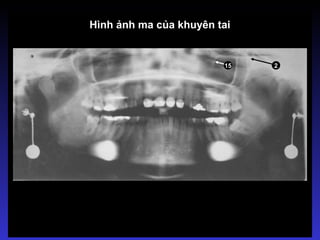

Hình ảnh ma

Thường là hình ảnh của các vật

thể ngoại lai nhưng cũng có thể

là hình ảnh của cấu trúc giải

phẫu nào đặc như cấu trúc của

xương hàm dưới.

Bóng của vật thể cản quang

nằm bên đối diện (khuyên tai,

cấu trúc giải phẫu nào đó)

Đặc điểm của hình ảnh ma:

 Nằm bên đối diện

 Cùng hình dạng

 Phóng to hơn

 Nằm cao hơn

 Mờ hơn

Hình ảnh ma của khuyên tai

15 2